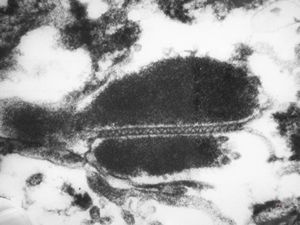

M,7m. | Birbeck granules (Langerhans granules, X-granules) - skin, histiocytosis X

M,7m. | Birbeck granules (Langerhans granules, X-granules) - skin, histiocytosis X

M,1y. | Birbeck granules (X-granules) - skin, histiocytosis X

M,1y. | Birbeck granule (X-granule) - skin, histiocytosis X